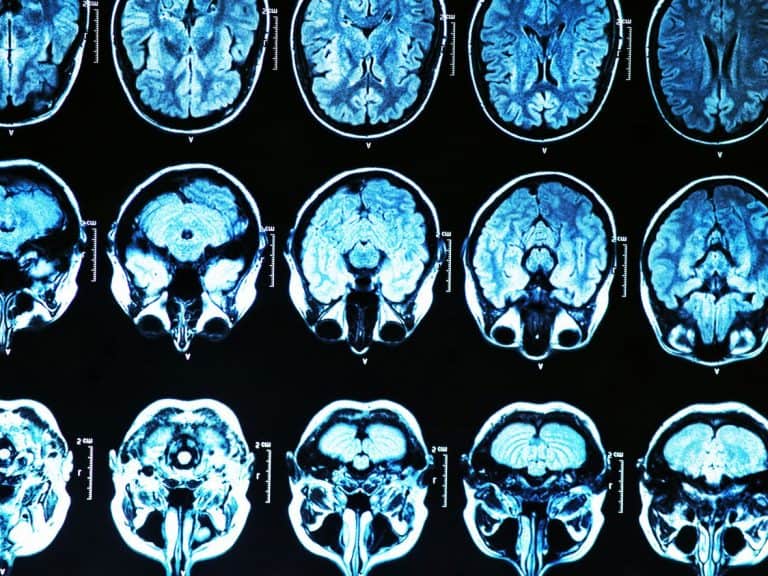

وهذا هو التأثير الذي يحاول الأطباء في كلية طب ويل كورنيل محاكاته. إذ يبحث المركز الآن عن أشخاص يحملون نسختين من الجين عالي الخطر ممن يعانون بالفعل من فقدان الذاكرة، أو حتى الإصابة بمرض الزهايمر. ويقول كريستال بأن أوائل المتطوعين سيتلقون بعد شهر تقريباً مليارات الفيروسات التي تحمل النمط 2 من الجين في الحبل الشوكي.

وبناءً على الاختبارات التي أجريت على القرود، يتوقع كريستال أن تقوم الفيروسات بنشر الجين الجيد إلى الخلايا في جميع أنحاء أدمغة المرضى. ووجد مركزه بأن بروتين الأميلويد تراكم بشكل أقل في أدمغة الفئران التي عولجت بالطريقة نفسها.

وتعدّ دراسة نيويورك أولية. إذ يقول كريستال بأن فريقه بحاجة إلى تحديد فيما إذا كان الجين المضاف يقوم بوظيفته على مستوى يمكن اكتشافه. سيقوم الأطباء بسحب السائل الشوكي من المرضى ومعرفة فيما إذا كان يحتوي على المزيج المتوقع من البروتينات، أي النمط 4 المتوقع، ولكنه يختلط الآن مع كمية مساوية لكميته أو أكبر منها من النمط 2.

عندما يبدأ الناس بنسيان الأسماء ومكان مفاتيح السيارة، فإن الأمر يكون نتيجة لتغيّرات الدماغ التي بدأت تحدث قبل عقد من الزمن. وهذا يعني بأن المرضى الذين سيشاركون في التجربة لا يمكنهم أن يتوقعوا الكثير من الفائدة. فربما فات الأوان بالنسبة لهم.